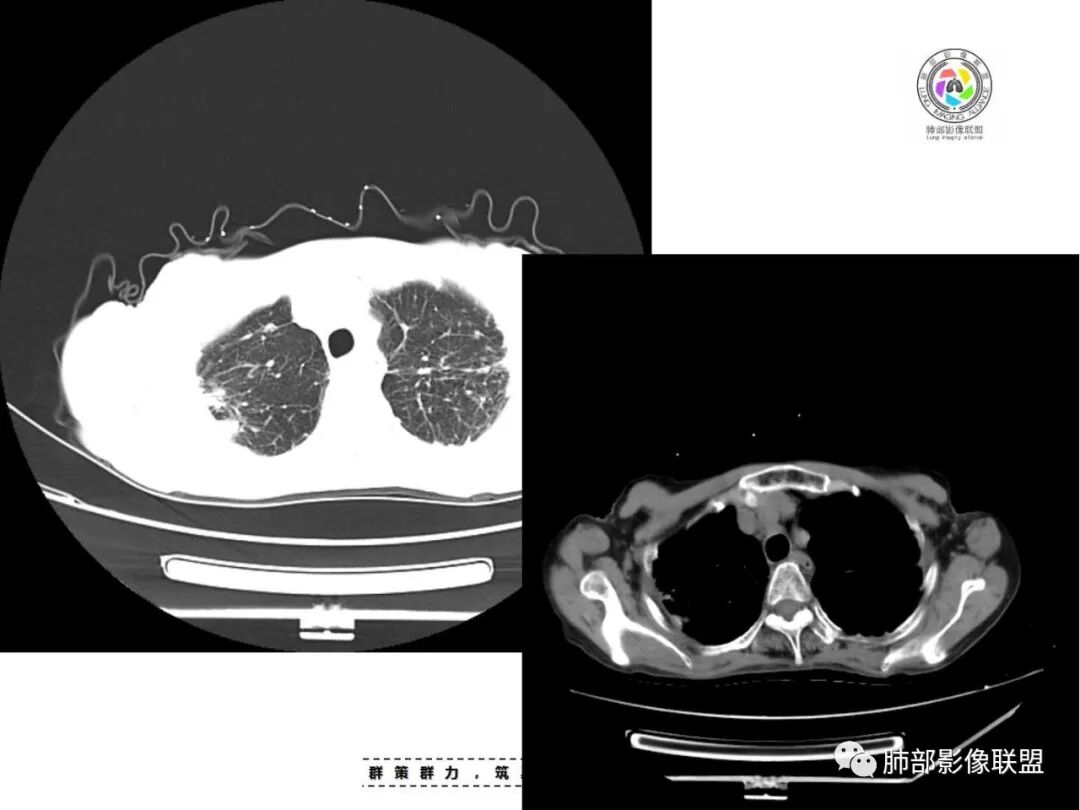

老年女性,67岁,咳嗽、咳痰半月余。双肺可闻及痰鸣音。

胸部CT:双肺上叶多发小结节,沿胸膜下、支气管血管束分布。右上肺斑片实变影、索条影及小叶间隔不均匀增厚,支气管枯枝征?纵隔淋巴结多发肿大,部分有钙化。综合考虑:结节病?尘肺?鉴别:腺癌并癌淋。

双侧胸膜下去多发结节状及斑片状实变影,周围伴有条索影,部分结节融合成小片状,中轴间质及小叶间隔增厚,纵隔淋巴结钙化,常规考虑结核,不除外合并尘肺。

支气管血管束是增厚的,多发病灶及纤维灶,有钙化及纵隔钙化淋巴结,树芽征,支持结核合并其他感染。

患者老年女性,亚急性起病,主要症状表现为咳嗽、咳痰半月余,查体:双现呼吸音粗,双肺可闻及痰鸣音。胸部CT:双上肺胸膜下可见多发小叶实变影,双上肺可见多发小叶中心性结节及小叶间隔增厚,右上肺后段可见亚段性实变影,内见多发空洞,前段可见GGO及树芽征,后段局部支气管闭塞,肺门淋巴结肿大并钙化。病灶整体:有气道、间质播散,一元论考虑肺结核合并支气管结核可能性大,建议好好查痰;这样病灶:明显实变+空洞+气道播散,若是结核,痰涂片找到抗酸杆菌应该没问题。建议支气管镜检查助诊,了解有无支气管结核及合并腺癌的可能。

*小结节,直径2-5mm,边缘清楚或不清楚,小叶中心性和胸膜下。

*弥漫分布,以上叶和后部为主,

*融合团块,形态不规则,含坏死区。

*淋巴结肿大和钙化。

1.双肺片状影、大小不等斑片影、结节影、树芽等,病灶密度偏高多钙化。

2.病灶上肺为主,胸膜下分布为主。双肺病灶明显不对称,右肺块状影较大。

1.胸膜下为主,簇状分布,大小不等,新旧不等,树芽,密度偏高等等都结核病变影像学特点。

2.多数尘肺结节影相对比较随机,没有胸膜下分布优势。

尘肺结节显得“游离”、清晰,一般较为均匀,很少呈多形性、斑片、树芽或新旧不等改变,晚期形成的纤维块状影多是双上肺中带对称分布,也很少纵隔偏移。

2.能够完全将尘肺排除在外吗(如II期)?不能!左肺内中带较均匀分布的较均匀是具有尘肺影像学特征而不支持结核血播的。此外双肺门及纵隔淋巴结钙化也更多见于尘肺,尤其是矽肺。